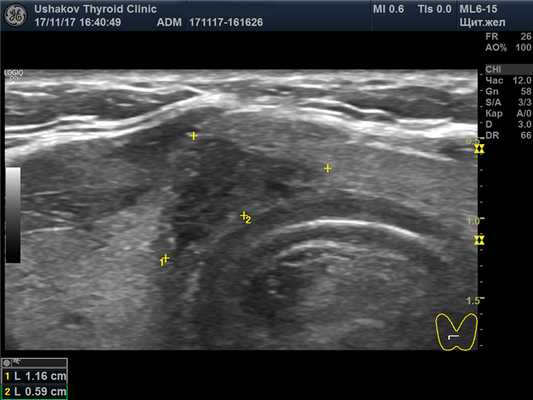

| Рисунок 1. В правой части перешейка щитовидной железы узел с признаками рака: 1) неправильная форма, вытянут не вдоль, а поперёк перешейка, 2) содержит значительно гипоэхогенную ткань, 3) граница узла в некоторых участках прерывистая. Класс по TI-RADS соответствует 4С. | Рисунок 2. Этот же узел в режиме ЭДК. Кровоток узла значительной интенсивности с признаками неупорядоченности распределения сосудов. |

| Рисунок 4. Узел верхней (краниальной) части правой доли щитовидной железы (ограничен желтыми метками). Признаки рака узла: 1) неправильная форма, 2) неравномерный край узла, местами прерывистая граница, 3) значительно гипоэхогенная (темная) зона внутри узла, постепенно переходящая в остальную ткань, 4) микрокальцинаты. Класс по TI-RADS соответствует 4С. | Рисунок 5. Изменённый регионарный лимфатический узел. Отношение сторон меньше коэффициента 2 (округлый), внутри определяется значительное разрастание ткани (признак метастазирования). |